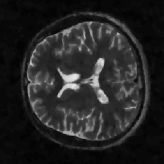

4 Experimental results

In this section, we present the experimental results on the phantom image and the real MR image used in [51], to compare the proposed DDTF based CS-MRI model Eq. 3.21 with several existing methods. We choose to compare with the total variation (TV) model [46]

We also set the maximum allowable number of iterations to be 600600600. To measure the quality of restored images, we compute the signal-to-noise ratio (SNR), the high frequency error norm (HFEN) [58], the number of iterations (NIters) to reach the stopping criterion, and the CPU time. Note that for the off-the-grid approaches Eqs. 3.21 and 4.3, the restored image is computed via the inverse DFT of the restored k-space data; see Fig. 2.

4.1 Phantom experiments

where J1subscript𝐽1J_{1} is the first kind Bessel’s function of order 111. Then using the variable density random sampling method in [46], we generate 20%percent2020\% undersampled k-space data. The complex white Gaussian noise is also added so that the resulting SNR of the samples is approximately 25dB25dB25\mathrm{dB} (See Fig. 3).

Refer to caption

(a) Fully sampled

(b) Ground truth

(c) Sample mask

(d) Undersampled

Figure 3: Dataset for the phantom experiments. Fully sampled k-space data, its inverse DFT as a ground truth, the undersampling mask, and the undersampled k-space data.